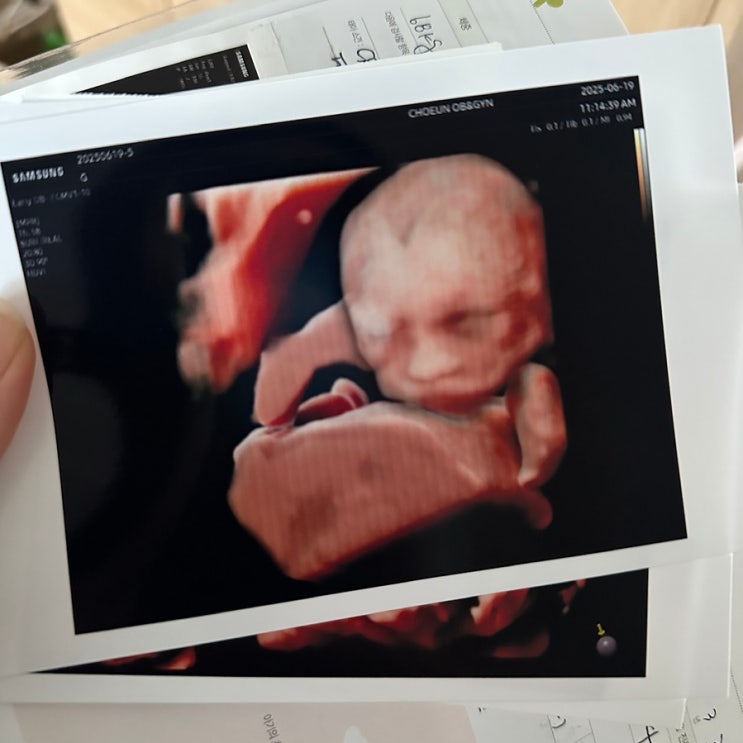

임신 16주-20주 기록 : 임산부 유방초음파, 입덧, 회, 피크닉, 부기와의 전쟁

벌써 20주까지의 기록을 남기게 되다니 시간이 정말로 빠른 것 같아요! 제 배는 하루하루 무럭무럭 커가고 ...